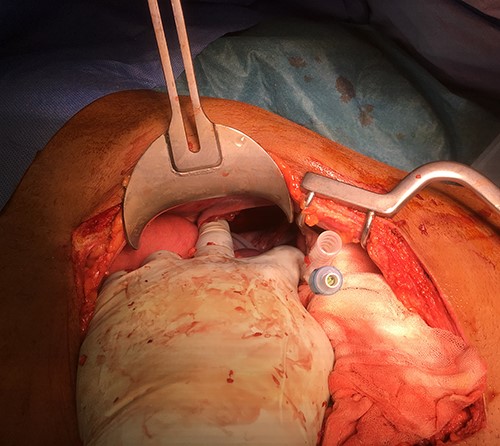

The patient was urgently taken to theatre for exploratory midline trauma laparotomy. Prophylactic antibiotics were administered. During surgery, a 10-cm defect of the left hemidiaphragm (Grade III [1, 2]) and 5-cm full-thickness stomach laceration (Grades II–III [3]) were identified along with contamination of the left hemithorax and abdominal cavity with a stomach content, a significant amount of chewed coconut (Figs 4 and 5).

Intraoperative photo after reduction of the ruptured stomach back to the abdominal cavity.